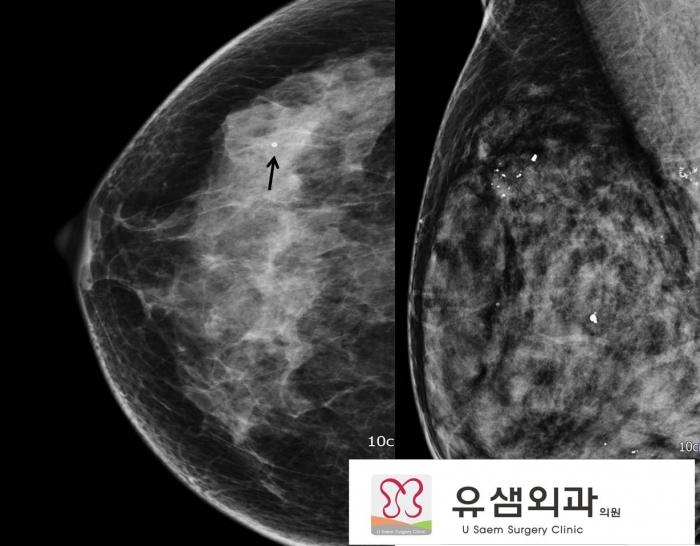

»çÁø1. ¾ç¼º ¼®È¸È . ¾ç¼º ¼®È¸ÈÀÇ ¿øÀÎ - ¿¹Àü¿¡

»çÁø 2. À¯¹æÃÔ¿µ ³»ÀÇ ¼®È¸È